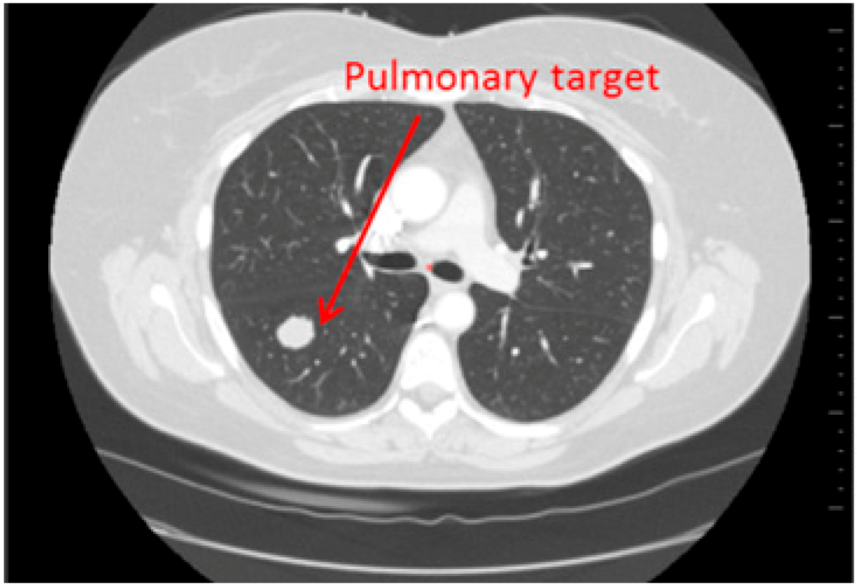

- 3D target matching technology to facilitate lesion localisation in the follow up study.

| Step 3 | Target localisation on baseline study | Manual | Automated |

| Step 4 | Target localisation on follow up study | Manual | Automated |